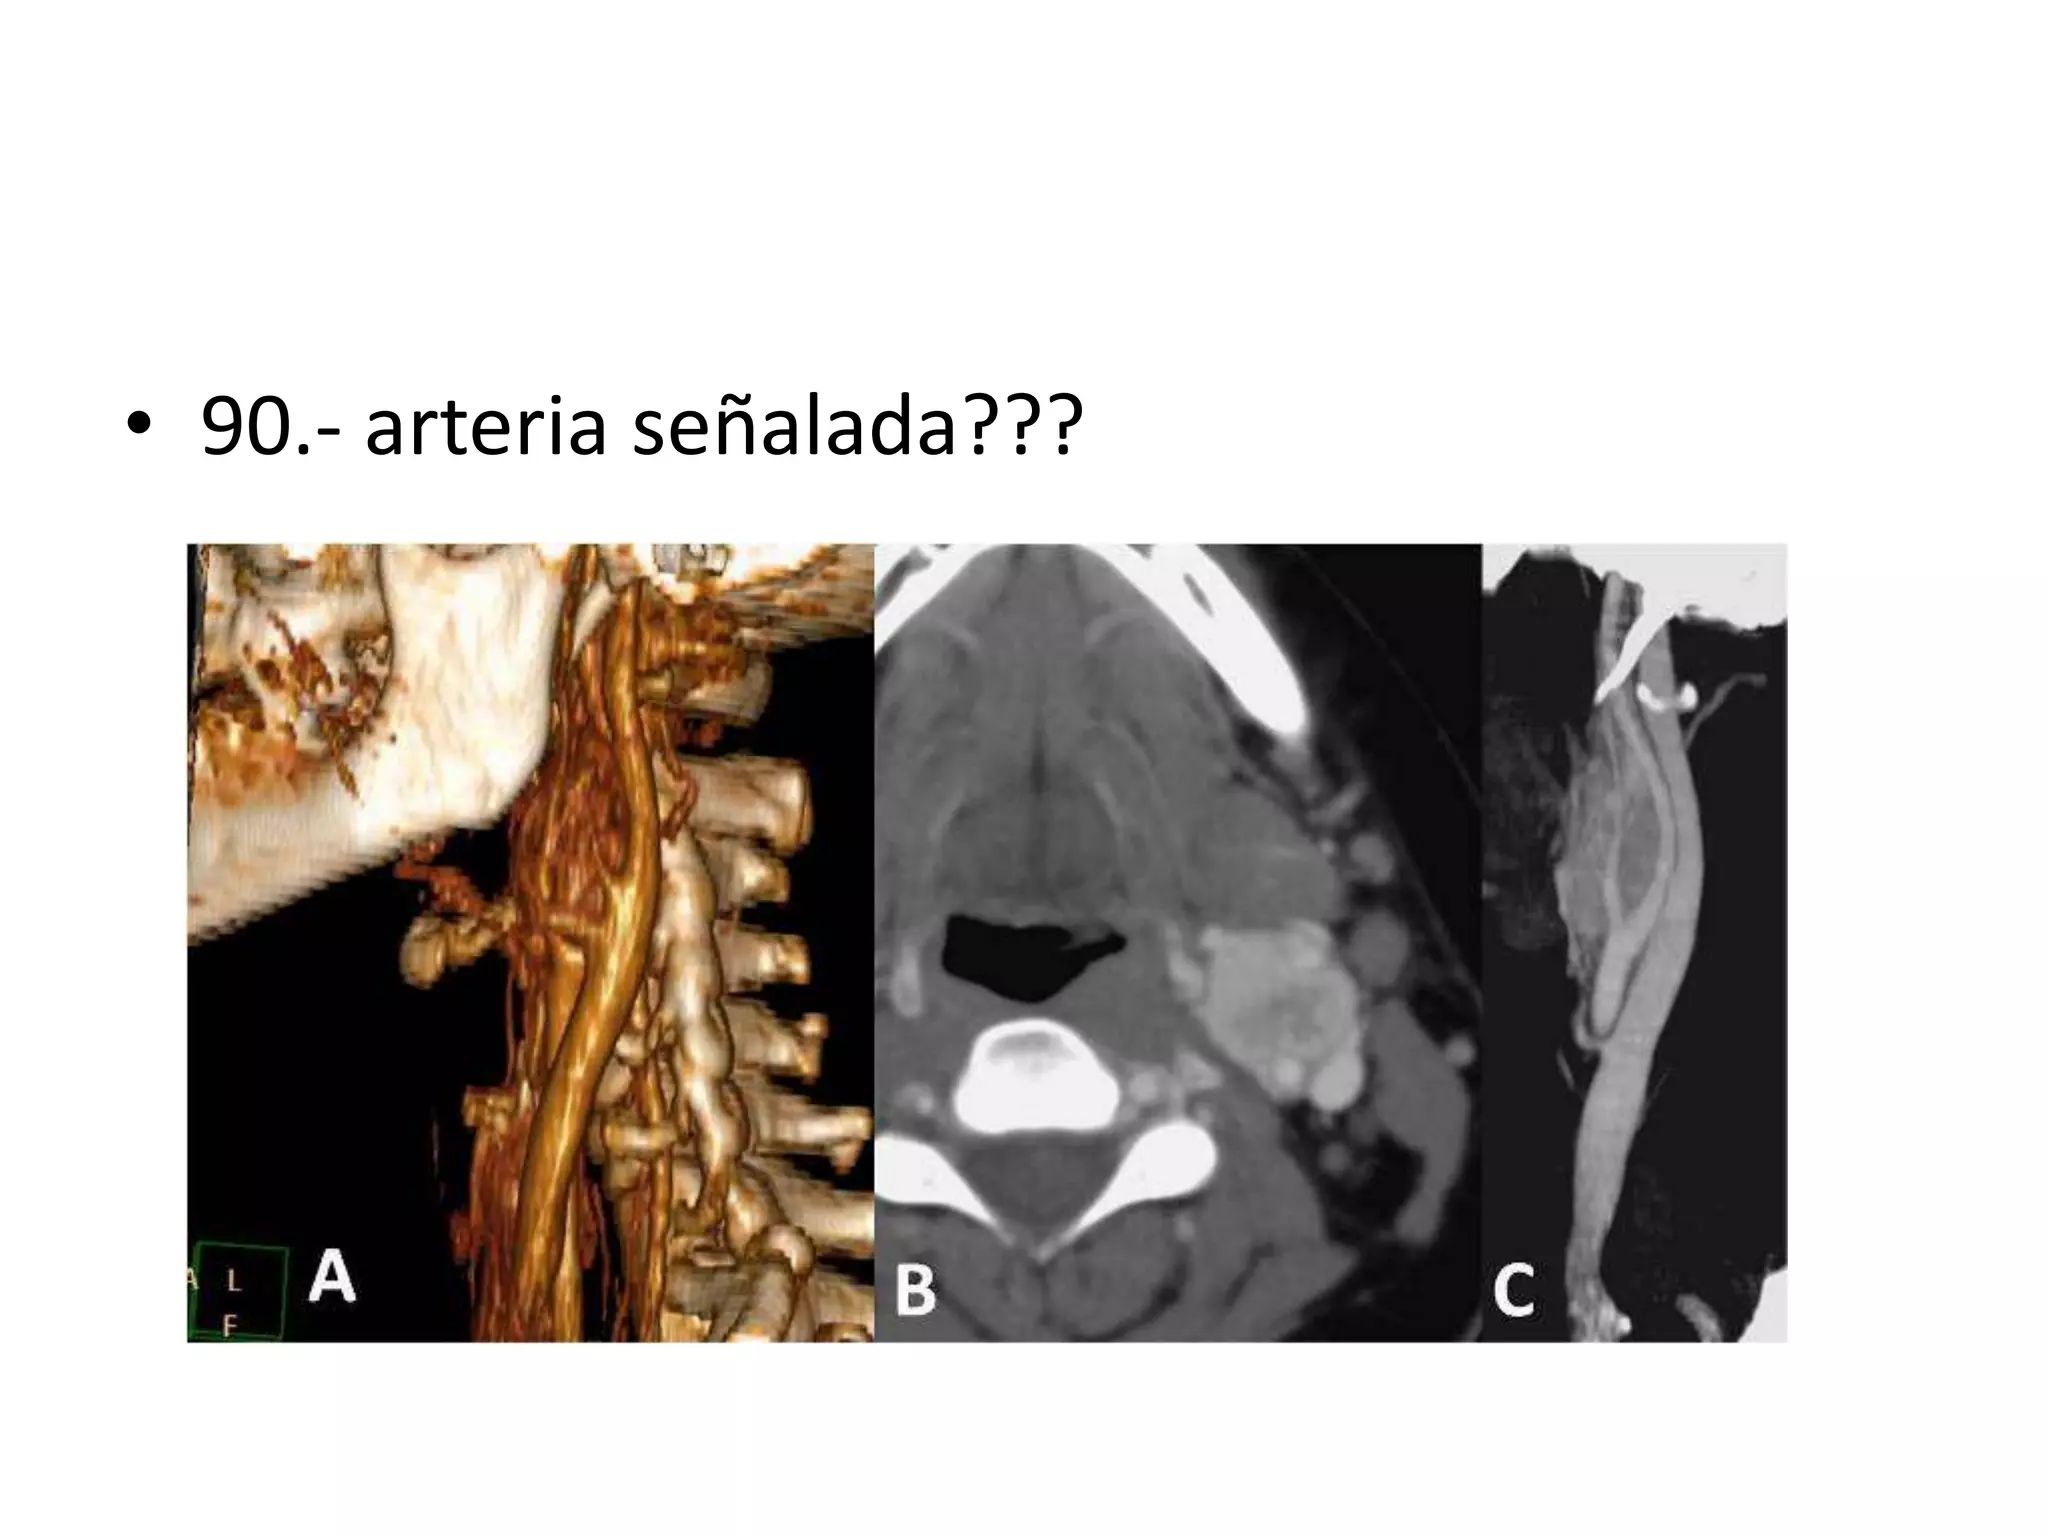

• 90.- arteria señalada???